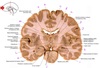

1

Q

a

body of corpus callosum

2

b

Anterior horn of lateral ventricle

3

c

Septum pellucidum

4

d

Rostrum of corpus callosum

5

e

Head of caudate nucleus

6

f

Anterior limb of internal capsule

7

g

Putamen

8

h

Nucleus accumbens